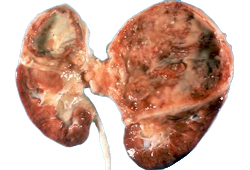

- Chronic pyelonephritis